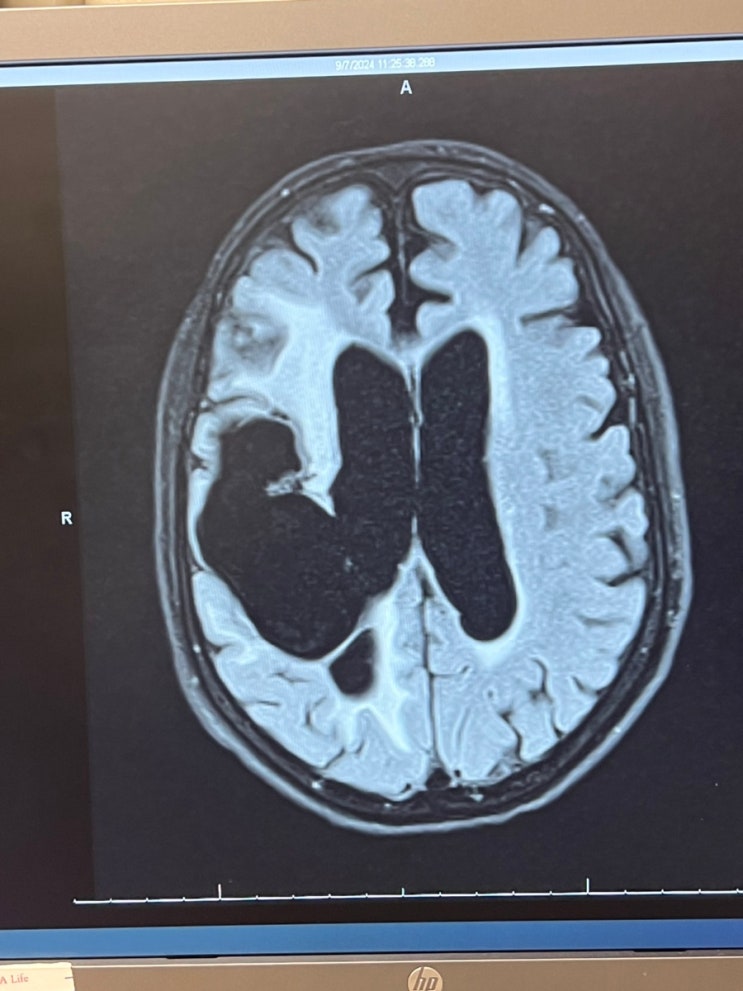

엄마 뇌사진

저번주 찍은 우리엄마 뇌사진. 내가 아무리 엄마가 나를 힘들게 해도 엄마를 끝까지 안고 살아가는 이유. ...